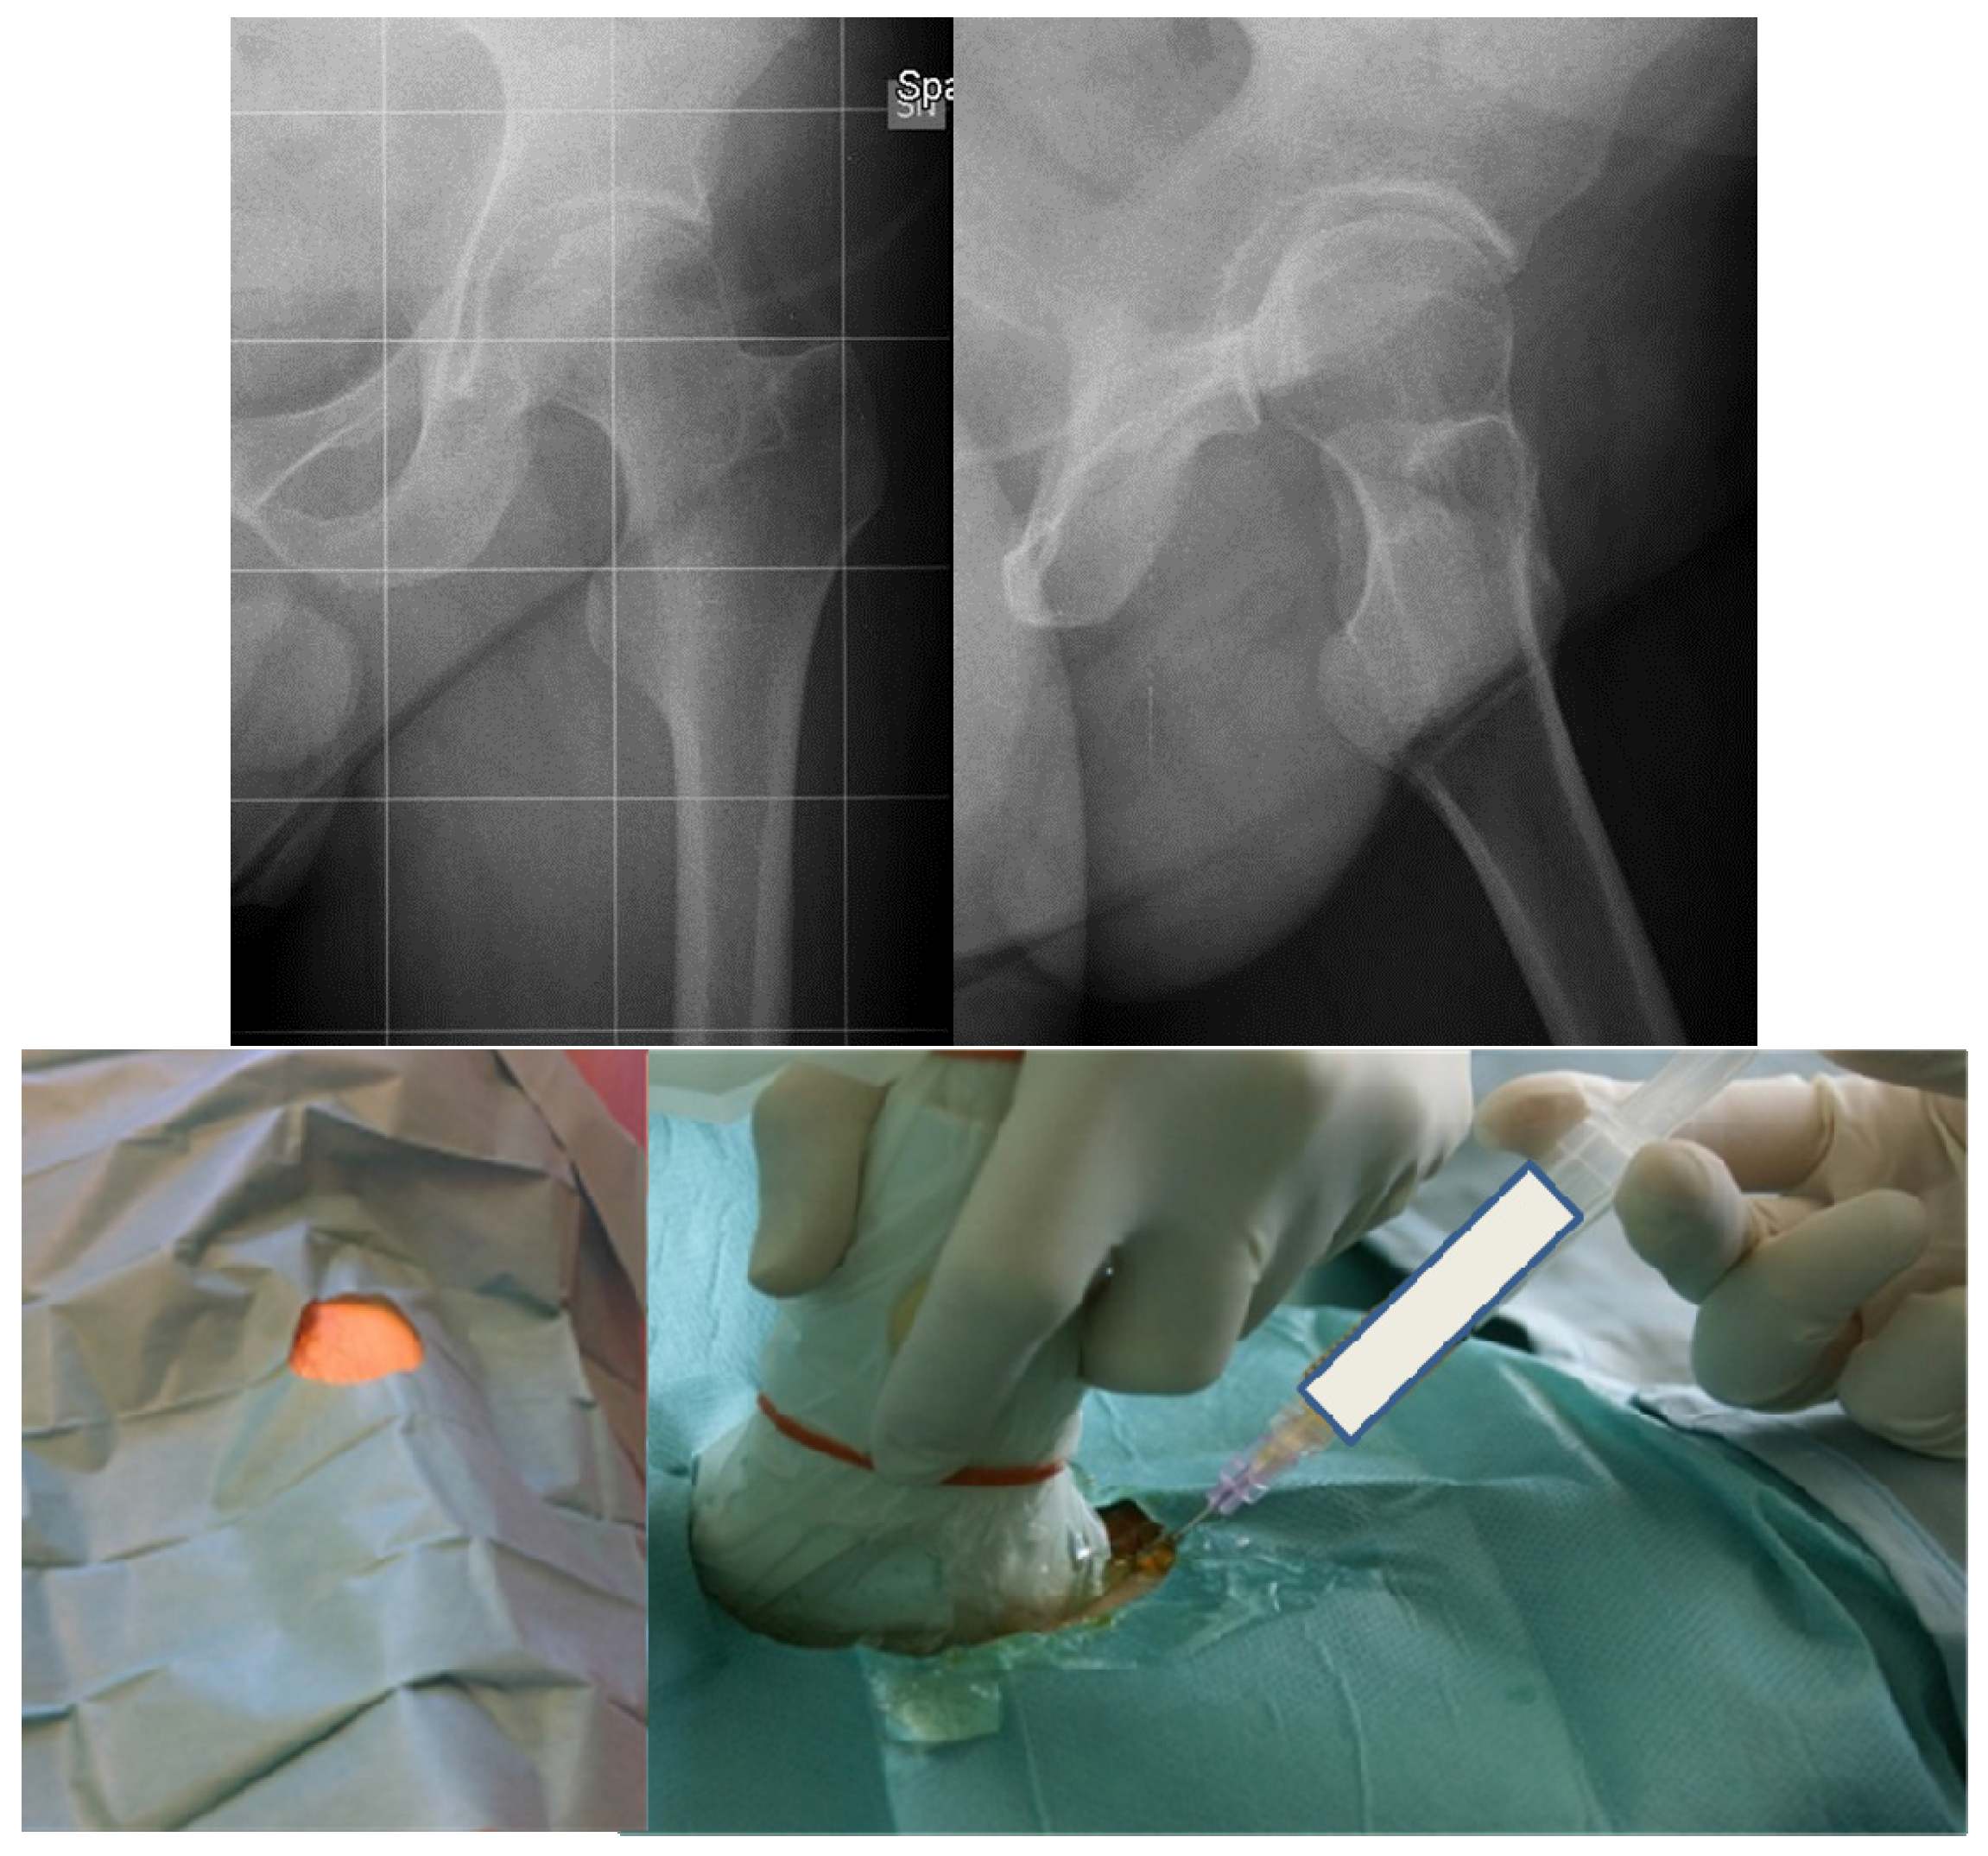

The haematological protocol with supplementation of the deficient factor is mandatory, if possible by a primary prophylaxis. In the case of arthropathy, in the early stages, a secondary prophylaxis is crucial to prevent the progression of arthropathy. As previously mentioned, the limitation of highly traumatic activities and the prescription of low-impact sports (mainly cycling and swimming) are proposed to improve the health status and global performance without loading the joints involved by haemophilia. Also, muscular toning exercises and stretching activity may be useful in young subjects to improve their functional ability or to recover it after a bleeding event. Anti-inflammatory drugs may be helpful in teenagers or adults combined with physical therapy. In the case of persistent symptoms (typically in the presence of active synovitis) and mild or moderate stages of arthropathy, something should be done to break the vicious circle leading to arthropathy. Intraarticular injections seem to provide good clinical effects and improve joint function in the hip, as well as in other target joints [5,6,7]. Several types of injections may be proposed: viscosupplementation by hyaluronic acid (HA); chemical synoviothesis by rifampicin or other antibiotics; radiosynoviorthesis by radionuclides; and injection with corticosteroids. Each drug has a specific purpose. HA is a polysaccharide containing glucosamine and glucuronic acid which are normally produced by synovial cells. Its effects are joint lubrication, shock absorption, and viscoelasticity of synovial fluid, but also stimulation of endogenous hyaluronic acid, anti-inflammatory effect, and inhibition of the degradative action of matrix metalloproteinases [8]. Viscosupplementation is usually proposed in symptomatic early stages of arthropathy when US examination excludes the presence of active synovitis in patients of all ages. Several experiences have been reported decades ago with encouraging short-term outcomes [9,10,11]. However, only one group proceeded with this approach in the long term, obtaining positive outcomes [5,6]. Viscosupplementation may also be considered for the treatment of hip disease with one to three injections (one per month), using US as a guide from the anterior aspect of the thigh in order to prevent any vascular or neurologic lesions (Figure 2).

Figure 2. Radiograms of a forty-eight-year-old haemophilic subject affected by severe haemophilia A with symptomatic left hip arthropathy treated by hyaluronic acid intraarticular injections in a sterile procedure.